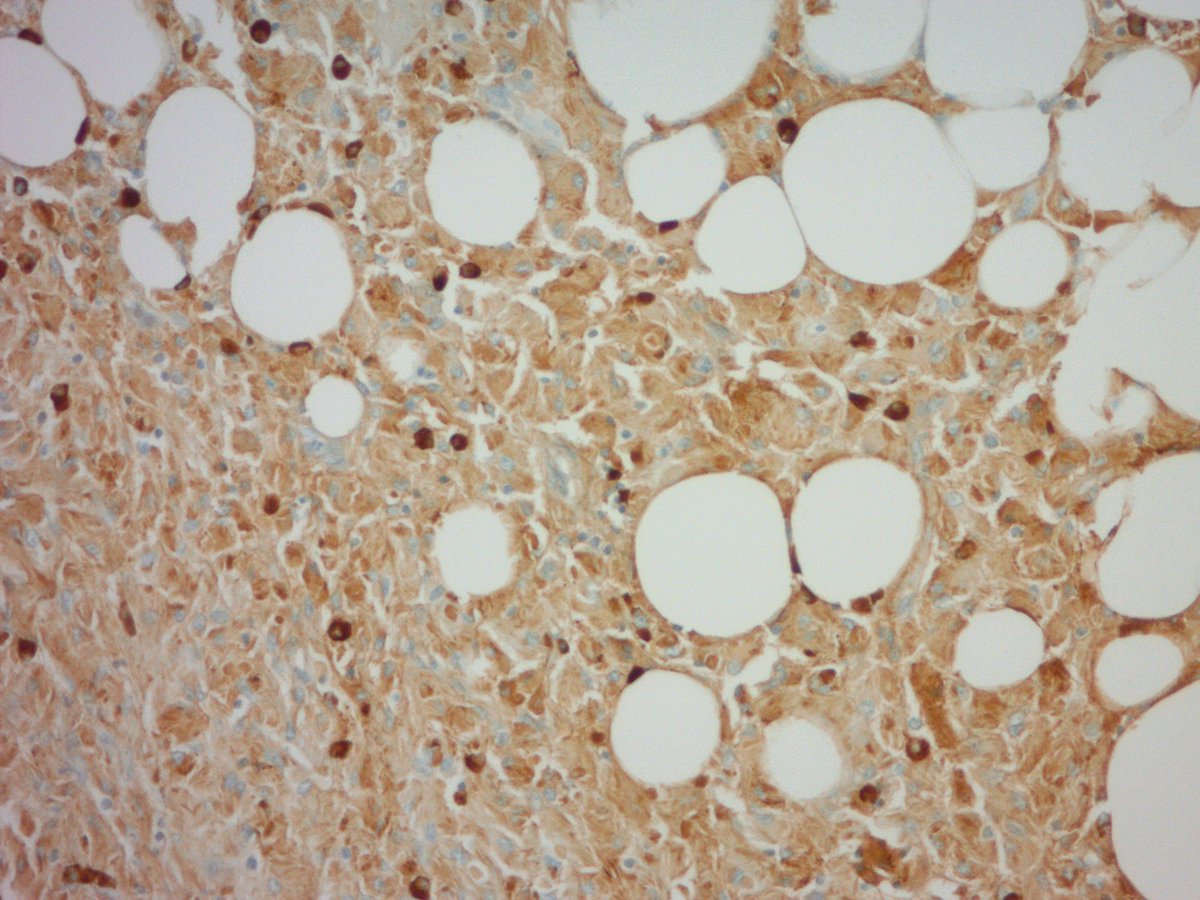

Biopsy of an incidentally discovered 5 cm well-circumscribed retroperitoneal mass abutting the bladder in a middle aged adult. Does anyone want to hazard a guess before I show the IHC? #BSTpath #pathology

jake_bledsoe's tweet image. Biopsy of an incidentally discovered 5 cm well-circumscribed retroperitoneal mass abutting the bladder in a middle aged adult. Does anyone want to hazard a guess before I show the IHC? #BSTpath #pathology